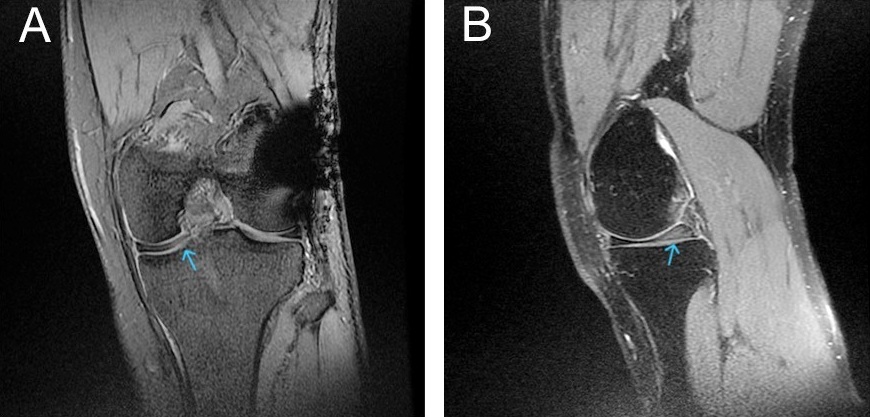

A probe was used to assess the repair’s tightness and stability. Post-operative management included partial weight-bearing with crutches, a full extension brace for 2 weeks, and initiation of isometric quadriceps exercises on the 1st day. Knee flexion to 90° was allowed at 3 weeks, with full ROM and progressive strengthening after 6 weeks. Return to sports occurred at 3 months. MRI of the contralateral knee revealed a discoid medial meniscus with mild degeneration signals and minimal symptoms, which were managed conservatively (Fig. 4).

Figure 4: Coronal (a) and sagittal (b) T2-weighted magnetic resonance imaging of the left knee showing an incomplete medial discoid meniscus with intrasubstance degeneration signals (arrow).